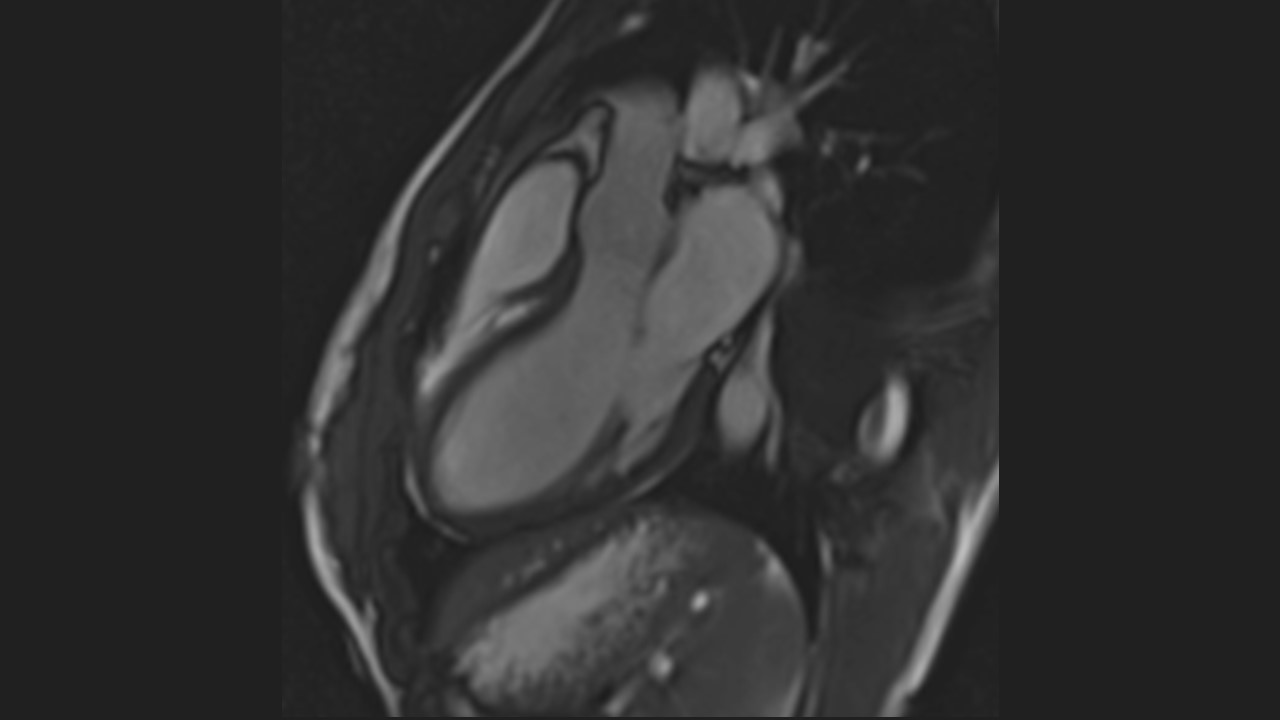

3 Chamber View